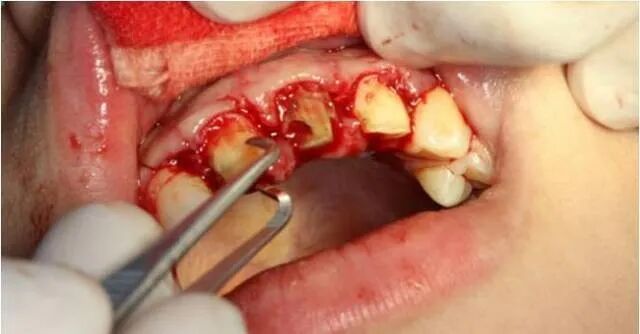

翻瓣后清除炎性组织